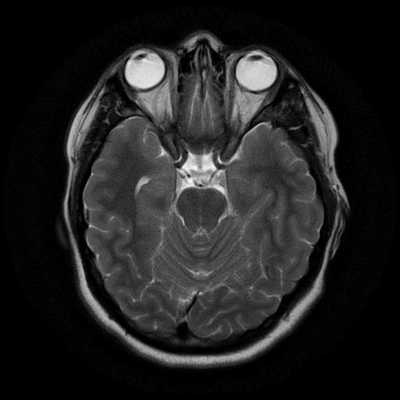

Классический пример МРТ снимков головного мозга показан на рисунках ниже. Магнитно-резонансная томография выполняется в поперечной (или аксиальной - рисунок снизу) и продольной (или сагиттальной — рисунок сверху) плоскостях.

Исследование выполняется в нескольких режимах. Основные из них Т1 и Т2. Изображения, полученные в данных режимах, часто также называют Т1-взвешенными или Т2-взвешенными снимками. Изображения, показанные выше, сделаны в Т1-режиме.

Главное отличие этих режимов - в том, как на снимках отображается жидкость и воздух. В Т1 режиме ткани, содержащие большое количество воды, имеют более темную окраску, в то время как в Т2 режиме они яркие, светлые. Это легко понять, посмотрев на снимки выше - глазные яблоки визуализируются в виде светлых парных округлых образований с одной стороны яркие и светлые, с другой - темные. Следовательно, снимок справа сделан в Т1 режиме, снимок слева - в Т2. Также существует разница в том, как в этих режимах отображается серое вещество головного мозга. В Т2 режиме оно светлее, чем белое вещество.